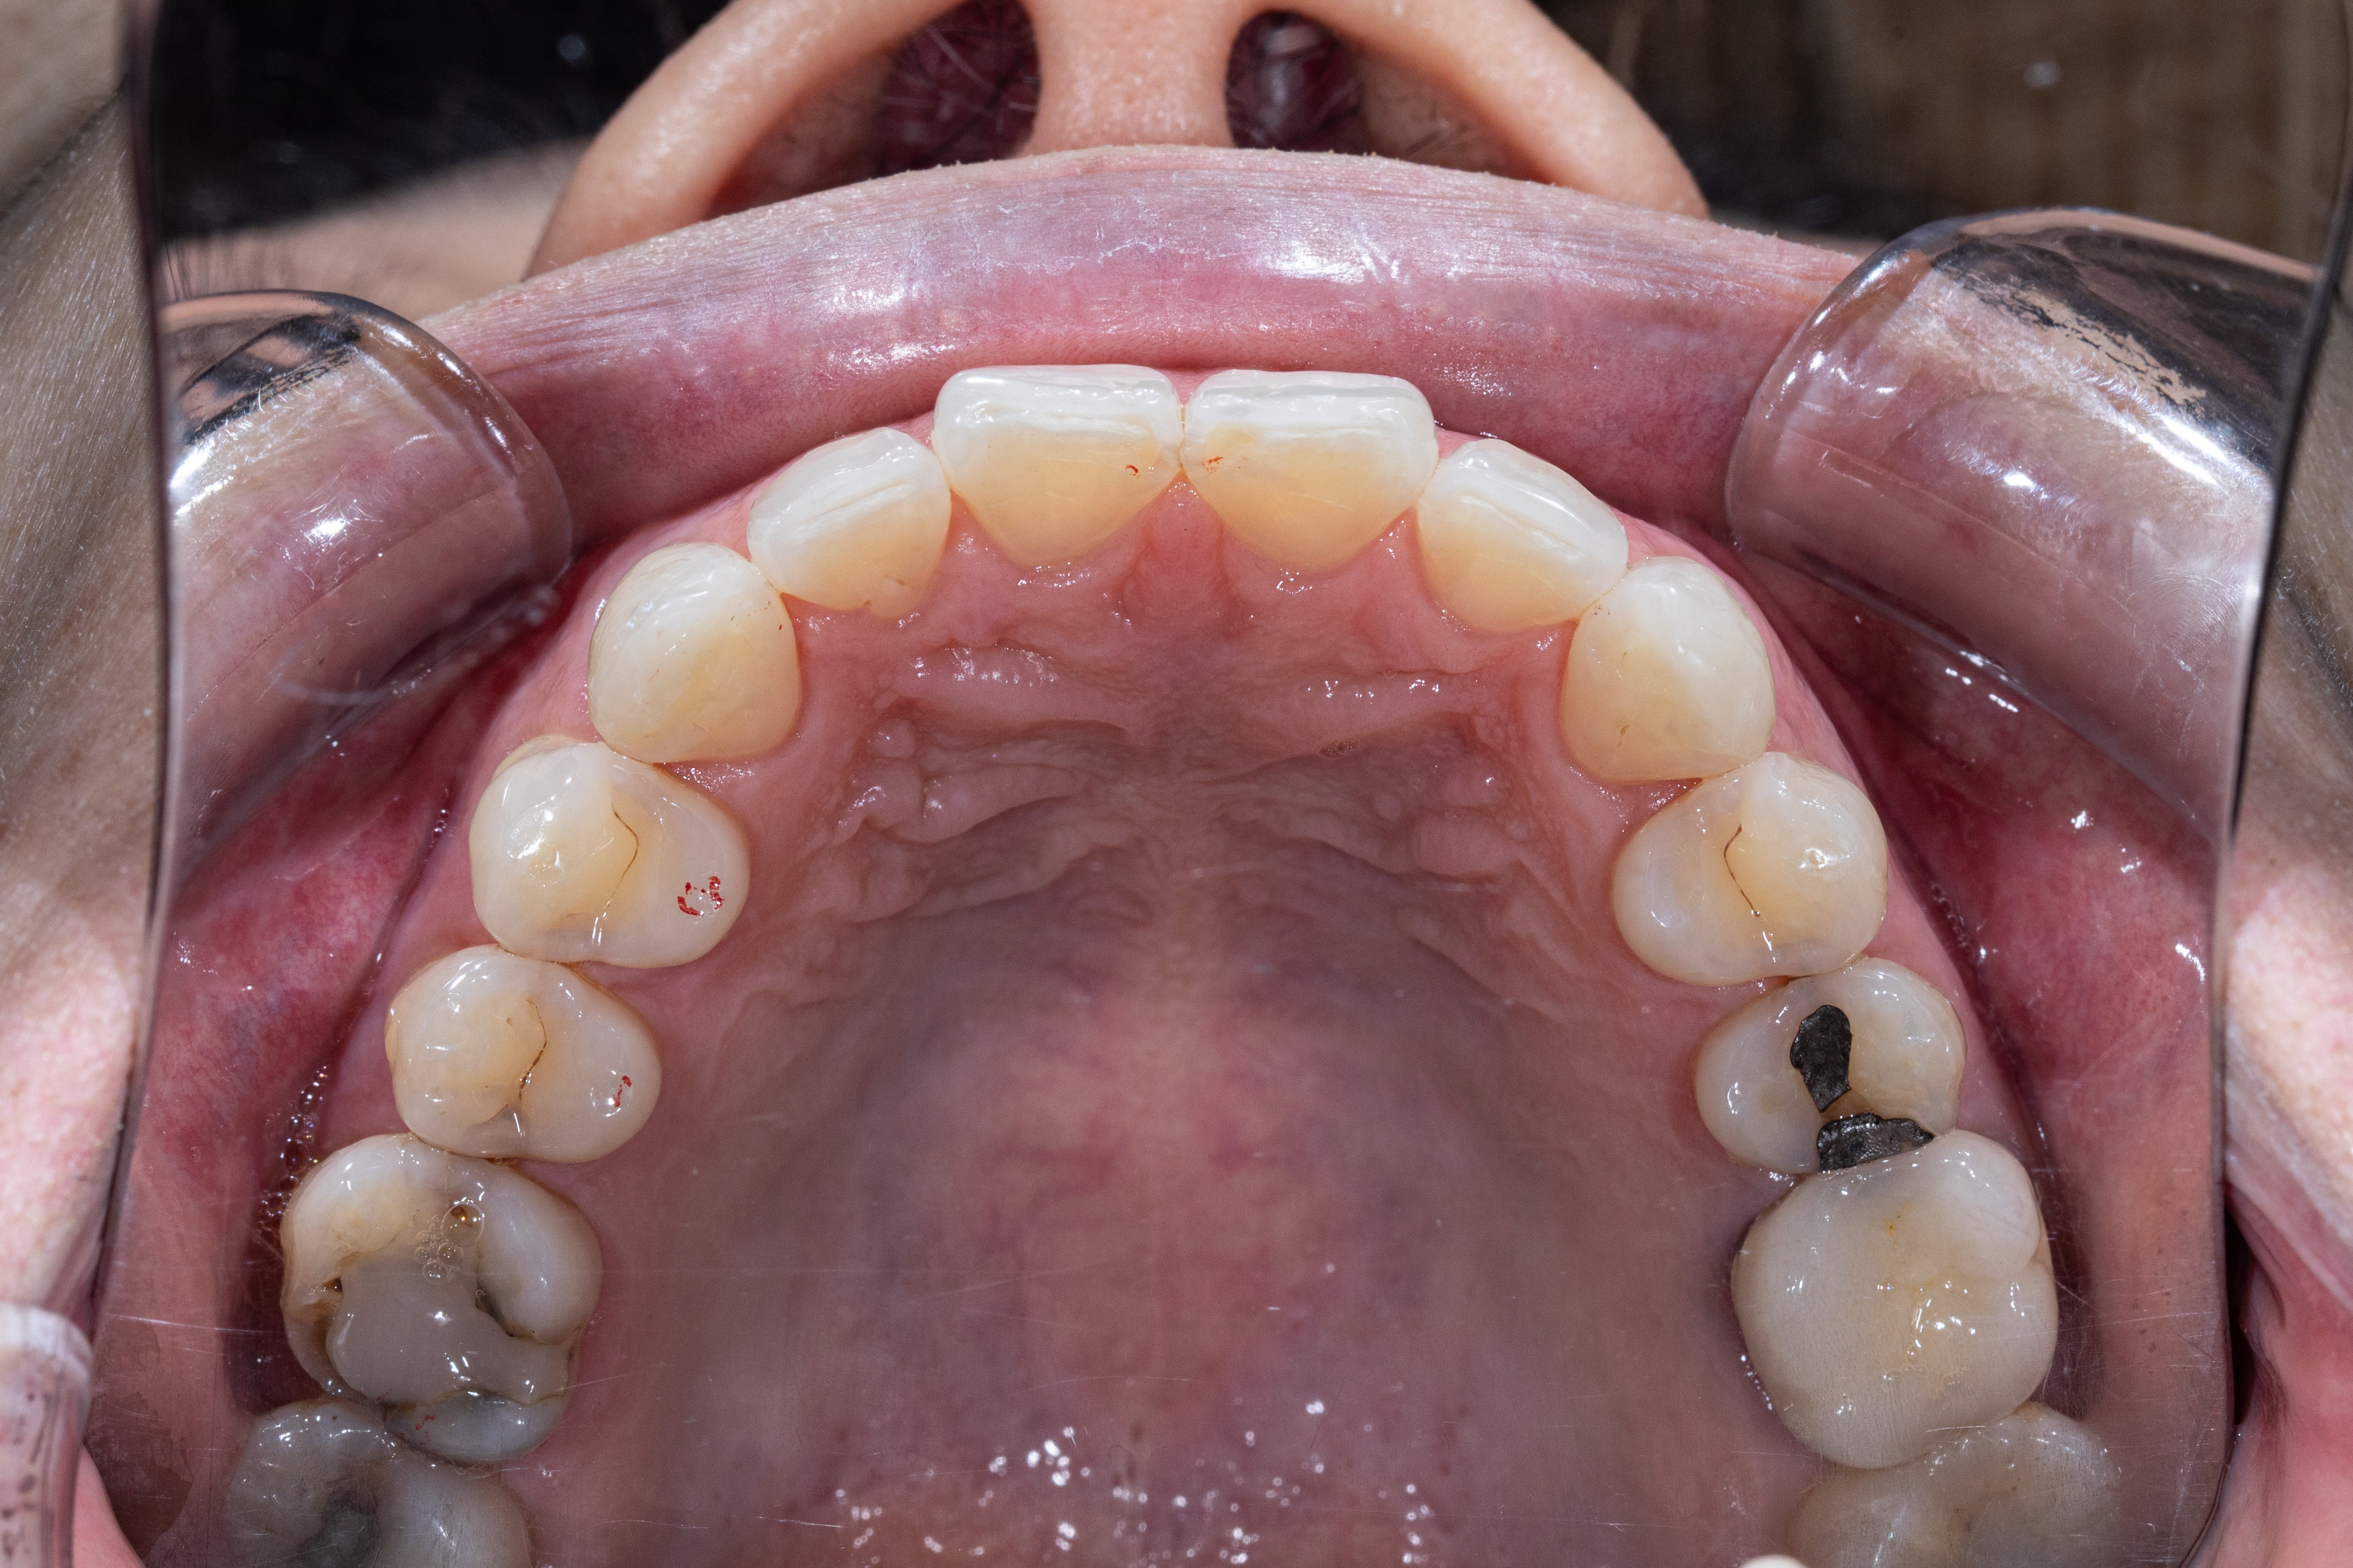

After

- 齒列排列不整,牙弓偏窄

- 咬合接觸不均,後牙支撐不足

- 優化牙弓形態

- 改善舌體與牙弓空間比例